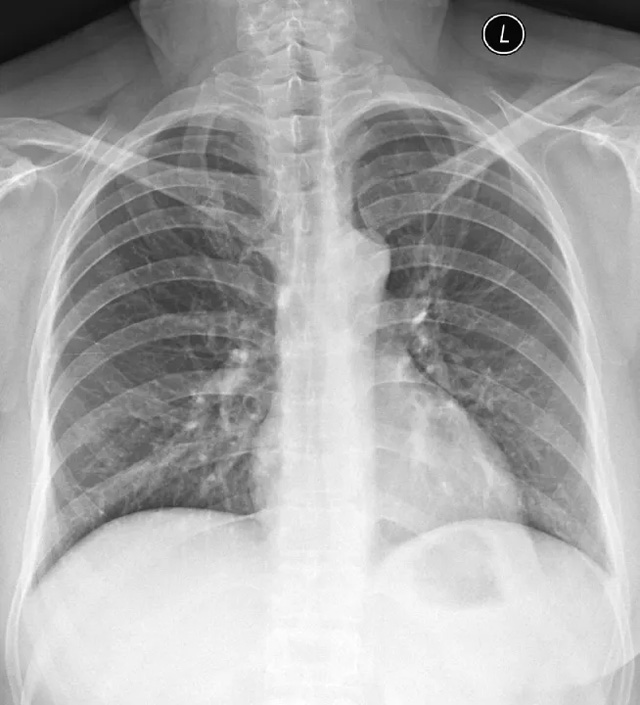

X线定位真空辅助旋切术是对临床触诊和B超检查均为阴性而X线片显示的微小病变在X线立体定位引导下,将真空旋切刀置入乳腺可疑病灶区进行旋切及组织病理学检查的一种乳腺微创新技术。

乳腺X线检查发现可疑微小钙化病灶成簇分布,BI-RADS:4类,且患侧乳房临床触诊和超声检查均为阴性。

部分BI-RADS 3类病灶,如果患者要求或临床其他考虑,也可考虑活检。

乳房体检扪及肿块,而乳腺X线提示相应位置有占位性病变,需要行微创活检或微创切除以明确诊断。

旋切范围主要是评估钙化灶的范围而定,如果钙化范围较大,仅仅是作为取活检的话,就旋切钙化相对集中的位置就行。如果需要达到旋切治疗的目的,那么仅仅是适合成簇的钙化,即2平方厘米的范围。